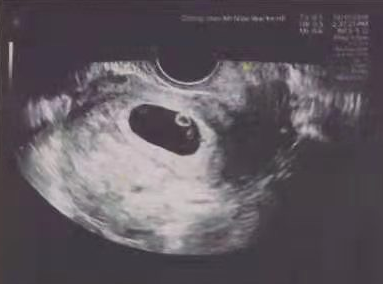

移植后的第11天,小方回医院抽血验孕,在看到验血结果的那一刻,小方哽咽得说不出话来,毕竟盼着这一刻真的挺久了。

这次顺利验得好孕,成功晋级当上妈妈。